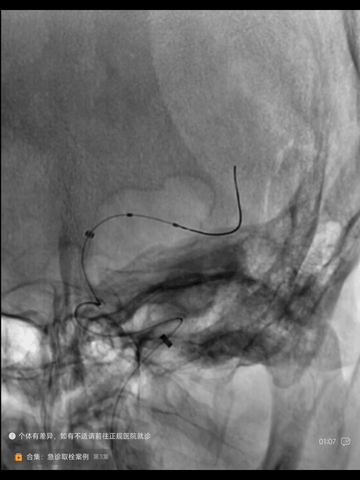

保持Transend导丝,在经中间管送入一synchro导丝,超选到下干M2,经此导丝送入一2*15mm球囊扩张下干起始部(2atm)

造影示下干恢复血流,其起始部狭窄亦明显改善,但左MCA主干出现一明显夹层

撤出synchro导丝,经Transend导丝送入微导管到M2,经微导管于左MCA主干植入一枚颅内自膨式支架(EP2 4*23mm),后造影示:支架位置佳,展开贴壁良好,主干狭窄解除,下干起始部未见明显狭窄。

术后症状快速恢复

出院NIHSS_0